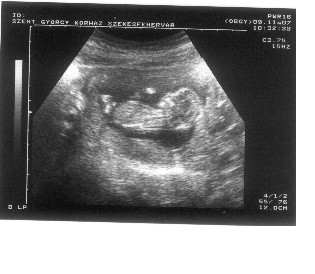

Kicsit ferdén sikerült a szkennelés, de annyi gond legyen. Itt a kis Titababa :)

Kép